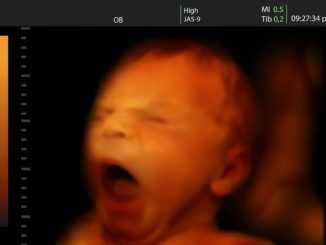

Anonimno svjedočanstvo o počinjenom pobačaju”Proslo je 7 godina otkad sam napravila ab. Pisem iz srca i po sjecanju, bez ikakvih izmisljanja da bi prica dobila na tezini. Jos uvijek me sram i nisam si oprostila.

Anonimno svjedočanstvo o počinjenom pobačaju“Proslo je 7 godina otkad sam napravila ab. Pisem iz srca i po sjecanju, bez ikakvih izmisljanja da bi prica dobila […]